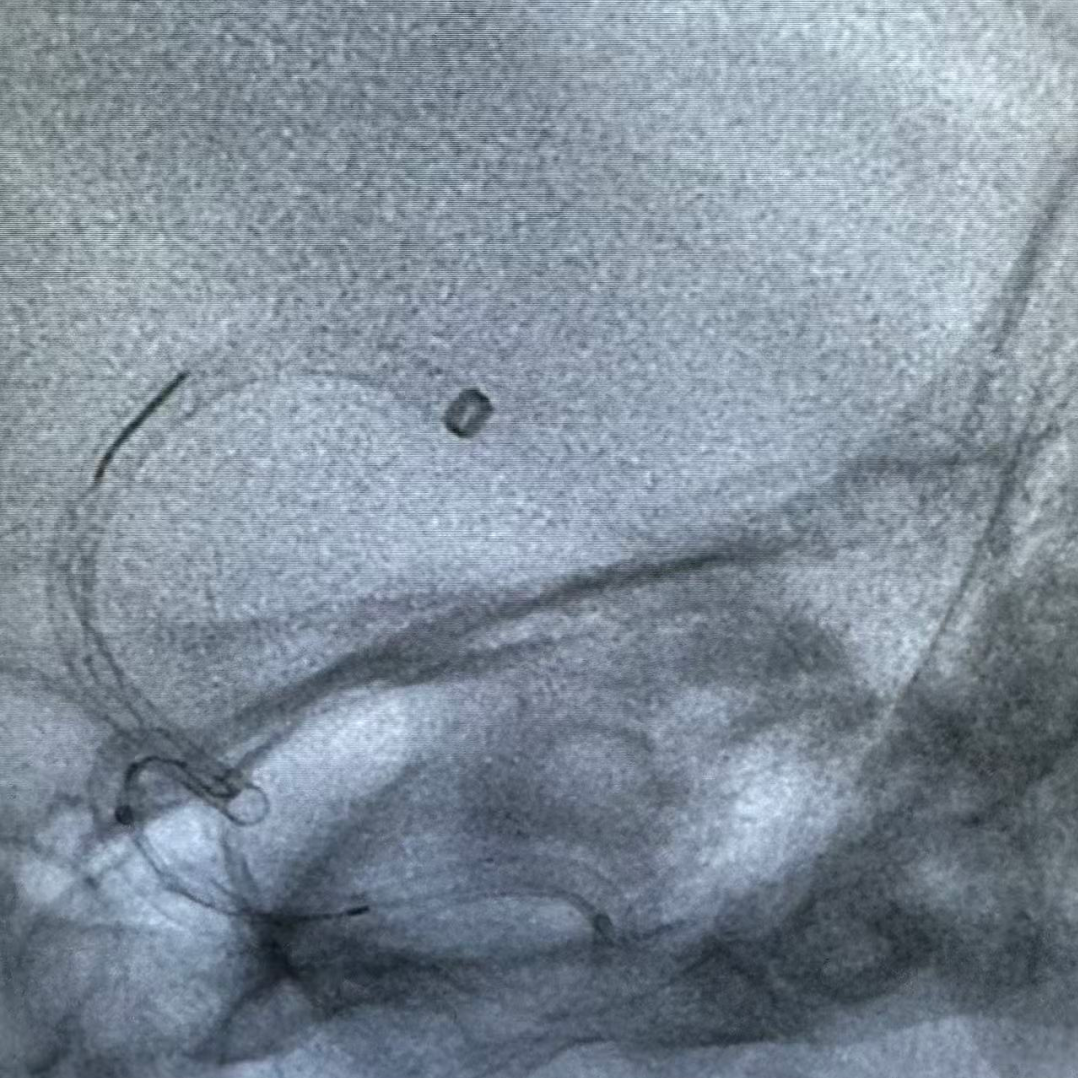

BMAX088球囊长鞘在泥鳅导丝及多功能管导引下顺利到达颈内动脉C1段。

微导丝微导管辅助下,6F中间导管前行,因海绵窦段血管较为迂曲,采用支架锚定跟进中间导管至血栓近端。

动脉长鞘怎么置入健谈•一鞘双能|温昌明教授团队:BMAX088球囊长鞘治疗左侧大脑中动脉闭塞一例_https://www.jmylbn.com_新闻资讯_第7张

动脉长鞘怎么置入健谈•一鞘双能|温昌明教授团队:BMAX088球囊长鞘治疗左侧大脑中动脉闭塞一例_https://www.jmylbn.com_新闻资讯_第8张

计划撤出内部器械前充盈近端BMAX088球囊长鞘,阻断前向血流,并持续抽吸提供负压。

取栓支架置于大脑中动脉水平段,中间导管在闭塞近端持续抽吸,在BMAX088球囊长鞘近端负压保护下,将支架及中间导管撤出。